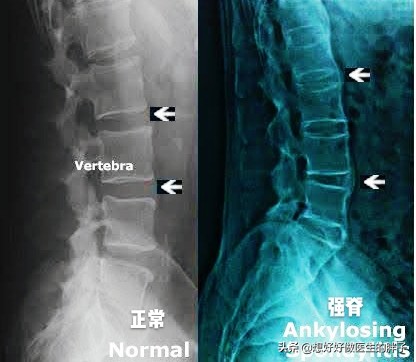

这个疾病最终在骨关节方面会导致整个脊柱(包括颈椎)严重的活动受限以及疼痛。很多患者的脊柱被逐渐的凝在了一起,而且会发生比较大范围的骨化,患者的脊柱由分节段的情况变成了类似竹节样融合在一起的状态,这是非常经典的一种强直性脊柱炎改变,我们称之为称之为竹节样改变。大家可以想一想,本来灵活多变的一个脊柱被逐渐凝在了一起,以后是否会发生活动的受限?是否会疼痛?

强直性脊柱炎中、晚期脊柱活动受限,检查x线可以发现典型的竹节样改变,诊断往往不难,早期诊断却容易和腰疼混淆,导致遗漏,早期的强直性脊柱炎患者以下的一些特点:

●脊柱x线检查,如果通过x线检查,能够看到明显的脊柱竹节样改变,可以作为诊断条件之一。